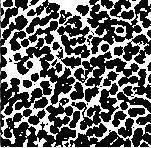

Binarization (Otsu’s thresholding):

Otsu's thresholding method, which is based on classification,seeksthethresholdthatreducesintraclass variance, which is determined by the weighted sum of variances for the two classes. The linear discriminant criteria used by Otsu's thresholding method presume thatapicturesimplyconsistsofobjects(foregroundand background),withtheheterogeneityanddiversityofthe backdrop being disregarded. To try to reduce the overlapping oftheclassdistributions, Otsu's established thethreshold.

Fig4:Binarizedimage(otsu’sthresholding)